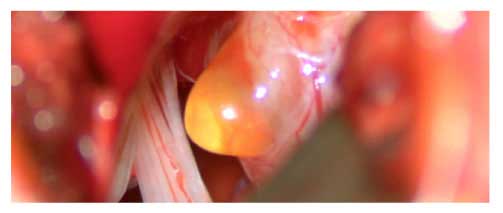

腦神經外科醫生會從多方面考慮及評估,制訂合適的治療方案。若腫瘤體積較細小和沒有症狀時,病人可以用保守治療方案定期覆診及檢查,如腫瘤體積較大又或壓迫到重要神經,病人有症狀及影響都較嚴重時,就要考慮接受微創顯微鏡手術切除。

保護聽覺神經及面部神經的微創顯微鏡手術

一般來說,微創顯微鏡手術切除是根治聽覺神經瘤的方法,但由於腫瘤與神經線和腦幹的緊密關係,手術過程有一定風險,尤其是聽覺神經受損導致聽力喪失,或是面肌神經受損以致面癱的可能性較大。然而經驗豐富的腦神經外科醫生會在顯微鏡下,以熟練精巧的手術,並利用手術中持續神經監測系統(Continuous Intraoperative Neural Monitoring System IOM),大大提高聽覺神經及面肌神經的功能保存。經驗豐富的腦神經外科醫生,腫瘤全切率達97至100%,面肌神經的功能保存率為51至98.2%,聽力保存率為19至40%,腫瘤復發率為5至10%。